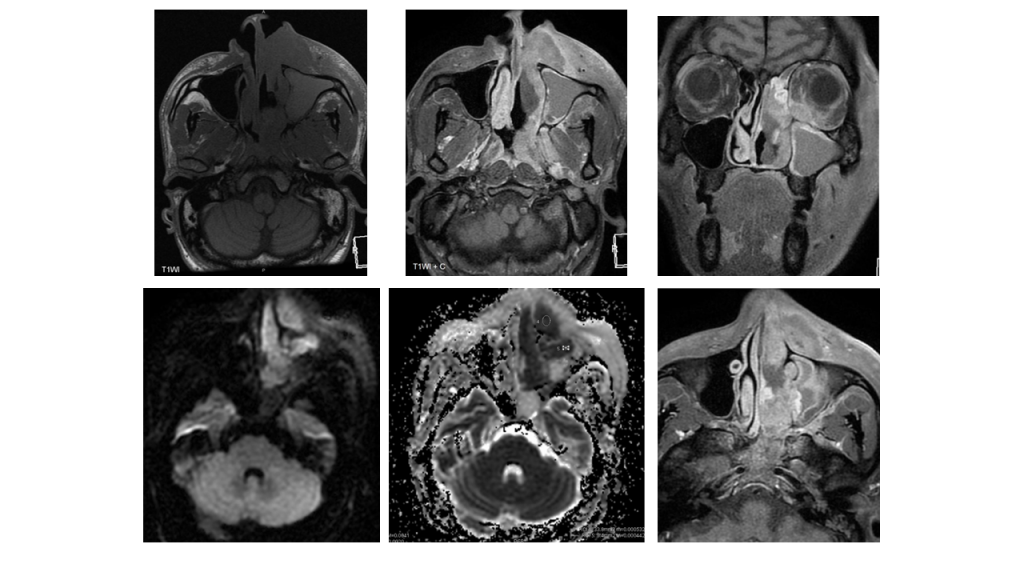

Linfoma extranodal tipo NK/T nasal

La TC es la primera técnica de imagen a realizar. Los resultados incluyen una masa sólida que se presenta en la cavidad nasal y que tiende a infiltrar las estructuras circundantes, con realce heterogéneo tras la administración de contraste. La destrucción leve del hueso se ve con frecuencia.

La RM suele mostrar una masa de tejido blando infiltrante y mal definida, con señal heterogénea en secuencias T1 y T2, y restricción a la difusión. A menudo hay componente necrótico presente.